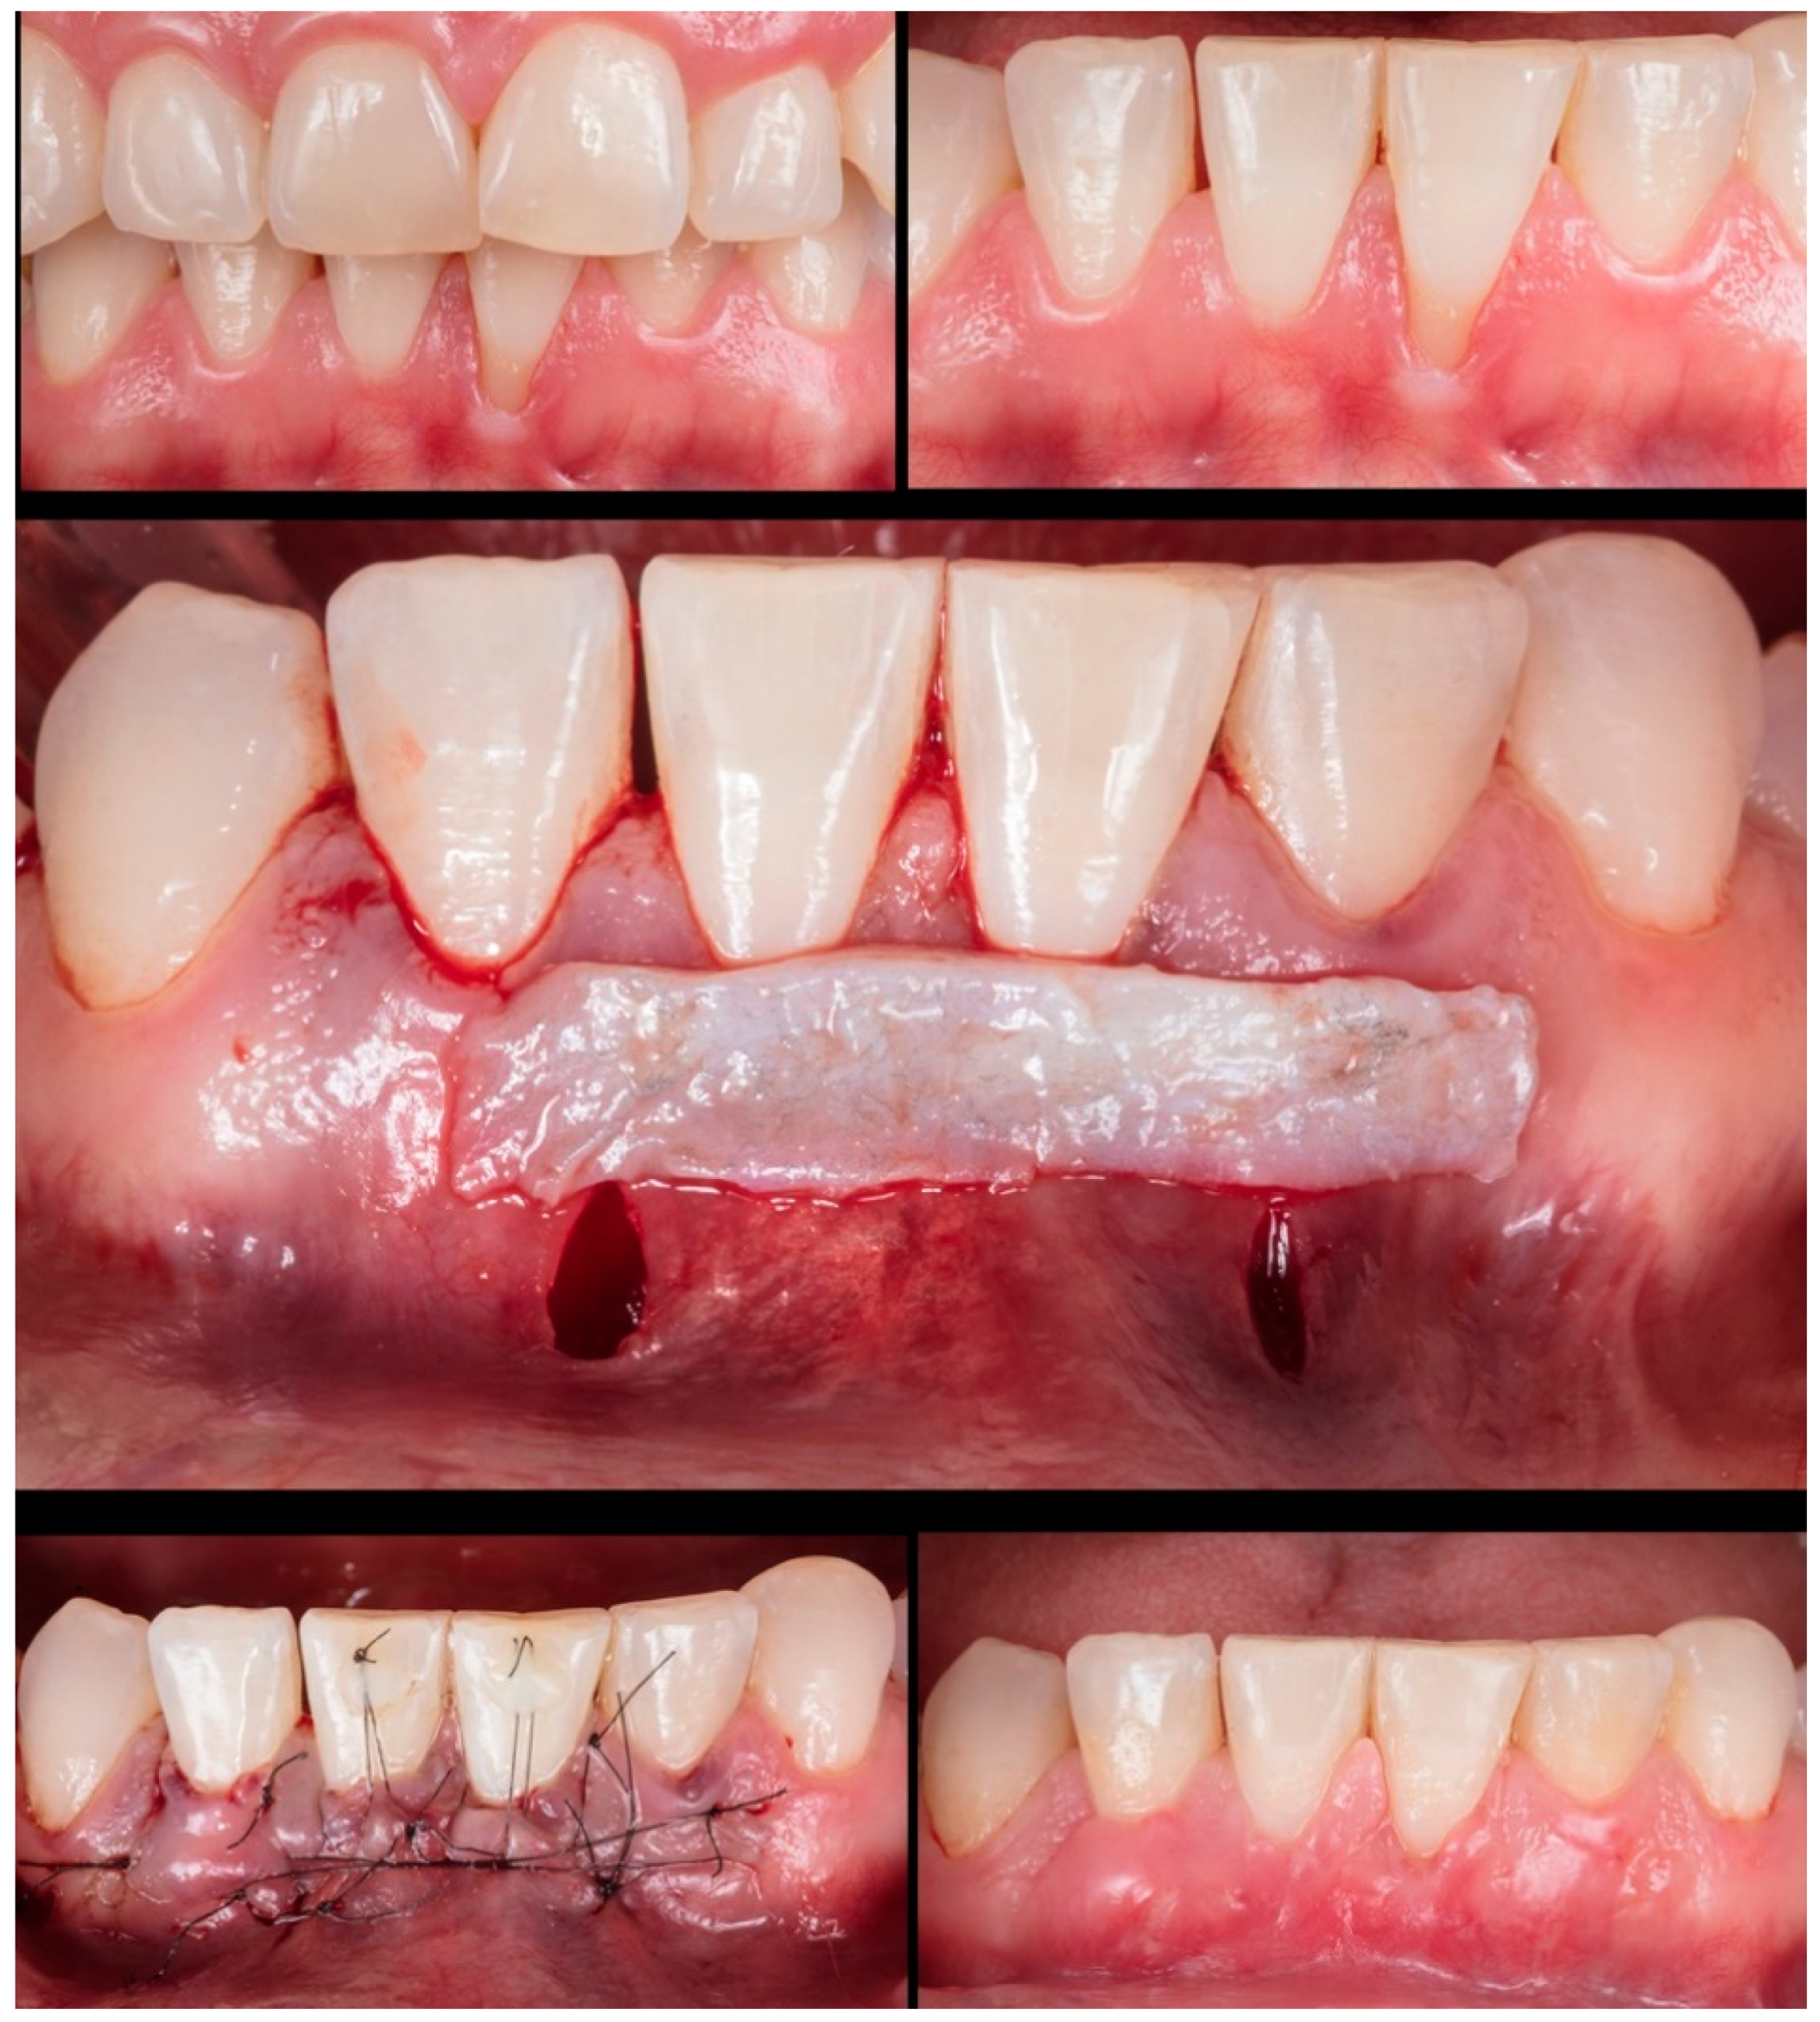

The last patient (9

th) was a RT1 case involving 2 adjacent teeth (#11-#12) in the esthetic region (

Figure 10). The recession height was 1mm and 2mm, respectively. The MiTT surgical steps were followed, and the suture was made with coronal traction of the tunnel, which was held by composites on the buccal face. After 30 days, it observed integration of the CTG with minor dehiscence and redness at the gingival margin. After 1 year, the healing improved, and complete root coverage was reached.

Figure 10.

Case 9 shows initial pictures of the GR defects (#12-#13); CTG already positioned through the vertical linear incision; a picture showing the final aspect immediately after surgery; and the healing period after 6 months.